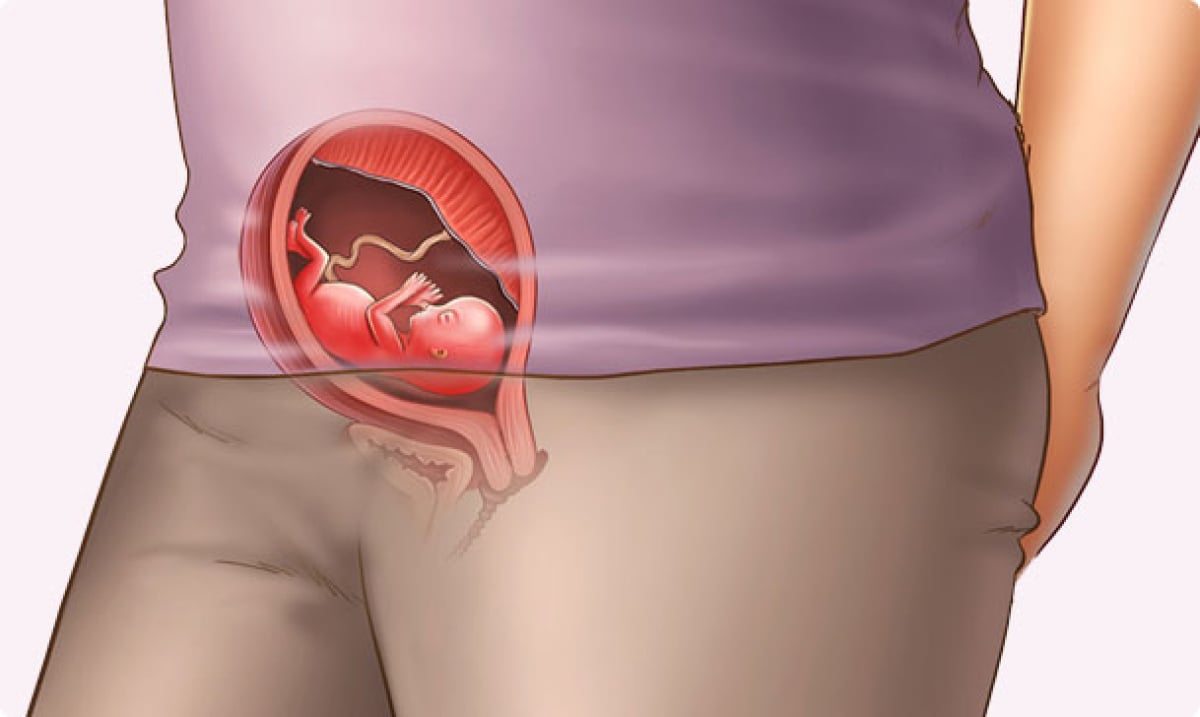

Расположение плода на 15-й неделе беременности: фотографии и иллюстрации